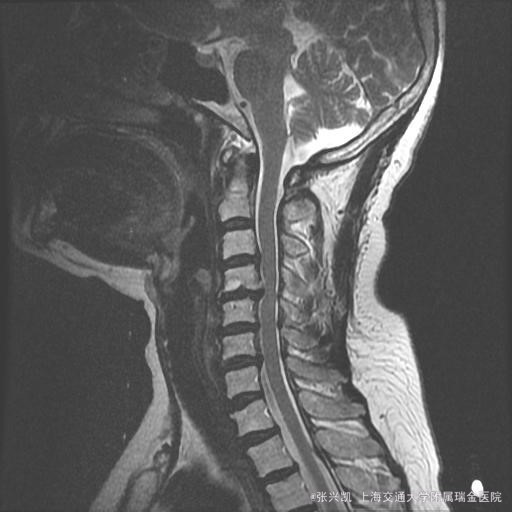

颈背部疼痛,双手手指麻木一年余 患者女性 ,今年59岁,一年前发生右手指麻木疼痛感,颈背部酸痛,后进行针灸推拿治疗,症状好转,但手指麻木越来越严重,后在当地医院检查诊断为颈椎病,具体治疗不详。现患者出现上臂疼痛,双侧指尖麻木,并伴有颈肩部疼痛,脚底无踩棉花感,下肢无感觉运动异常。

查体:脊柱无侧弯畸形,肩背部压痛,压头试验(+),双侧肌力肌张力可,双侧指尖至手肘感觉麻木疼痛。肱二头肌三头肌反射(+)。下肢肌力可,膝腱反射正常,巴氏征阳性。 颈椎MRI示:C3-7椎间盘突出伴后纵韧带骨化,C5-6水平椎管狭窄,脊髓受压 颈椎正侧位:颈椎曲度变直,退行性改变

诊断:颈椎椎管狭窄 OPLL 治疗:颈椎后路椎板成形术